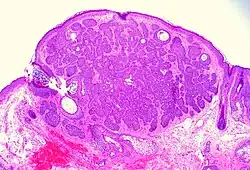

![Fibroepitheliomatous pattern (anastomosing basaloid epithelial strands enclosing round islands of fibrous stroma)[36]](./_assets_/Micrograph_of_basal-cell_carcinoma_with_fibroepitheliomatous_pattern.jpg)